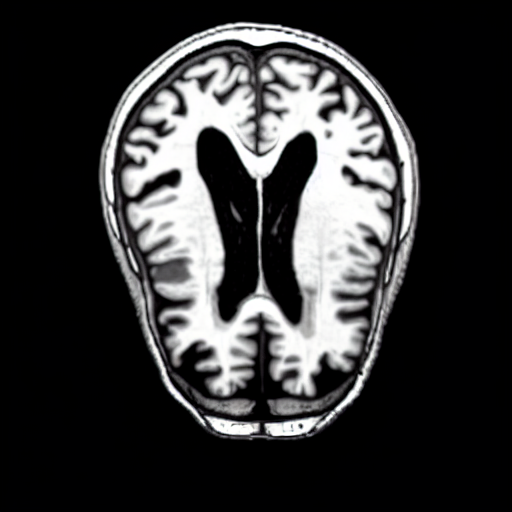

Qualitatively, Fig. 5 shows a significant improvement of the visual realism across all methods when using a drift of . The background is consistently black as in real brain MR images; the shape of the brain becomes more realistic, and the white and gray matter structure improves. For an analytical evaluation, we calculated the FID between our test data and 200 synthetically generated images from each method (100 CN, 100 AD). The results in Tab. 1 demonstrate that LD improves the ability of the model to generate realistic MRI slices for both healthy brains and brains with Alzheimer’s disease. For this reason, all following experiments were done with LD.

We use the Pix2Pix Zero model with a basic fine-tuned Stable Diffusion model to generate healthy brain MRIs from ones diagnosed with Alzheimer’s Disease and vice versa. We generate the counterfactual images by negating the ground truth label of the 200 test samples and conditioning the model on the negated label value and the source image. We compute image quality metrics, as well as the AUC, using a disease classification model trained on 600 real brain MRI slices (300 AD, 300 CN). Additionally, we determine the Structure Similarity Inced (SSIM) between the target and the source image to determine how well the identity of the source image is retained. The qualitative results in Fig. 6 , illustrate four examples from our two editing directions: from AD to CN and from CN to AD, respectively. When transitioning from AD to CN, the model primarily reduces the size of the ventricles. Conversely, in the CN to AD transformation, the ventricle size increases, accompanied by a worsening of brain atrophy.